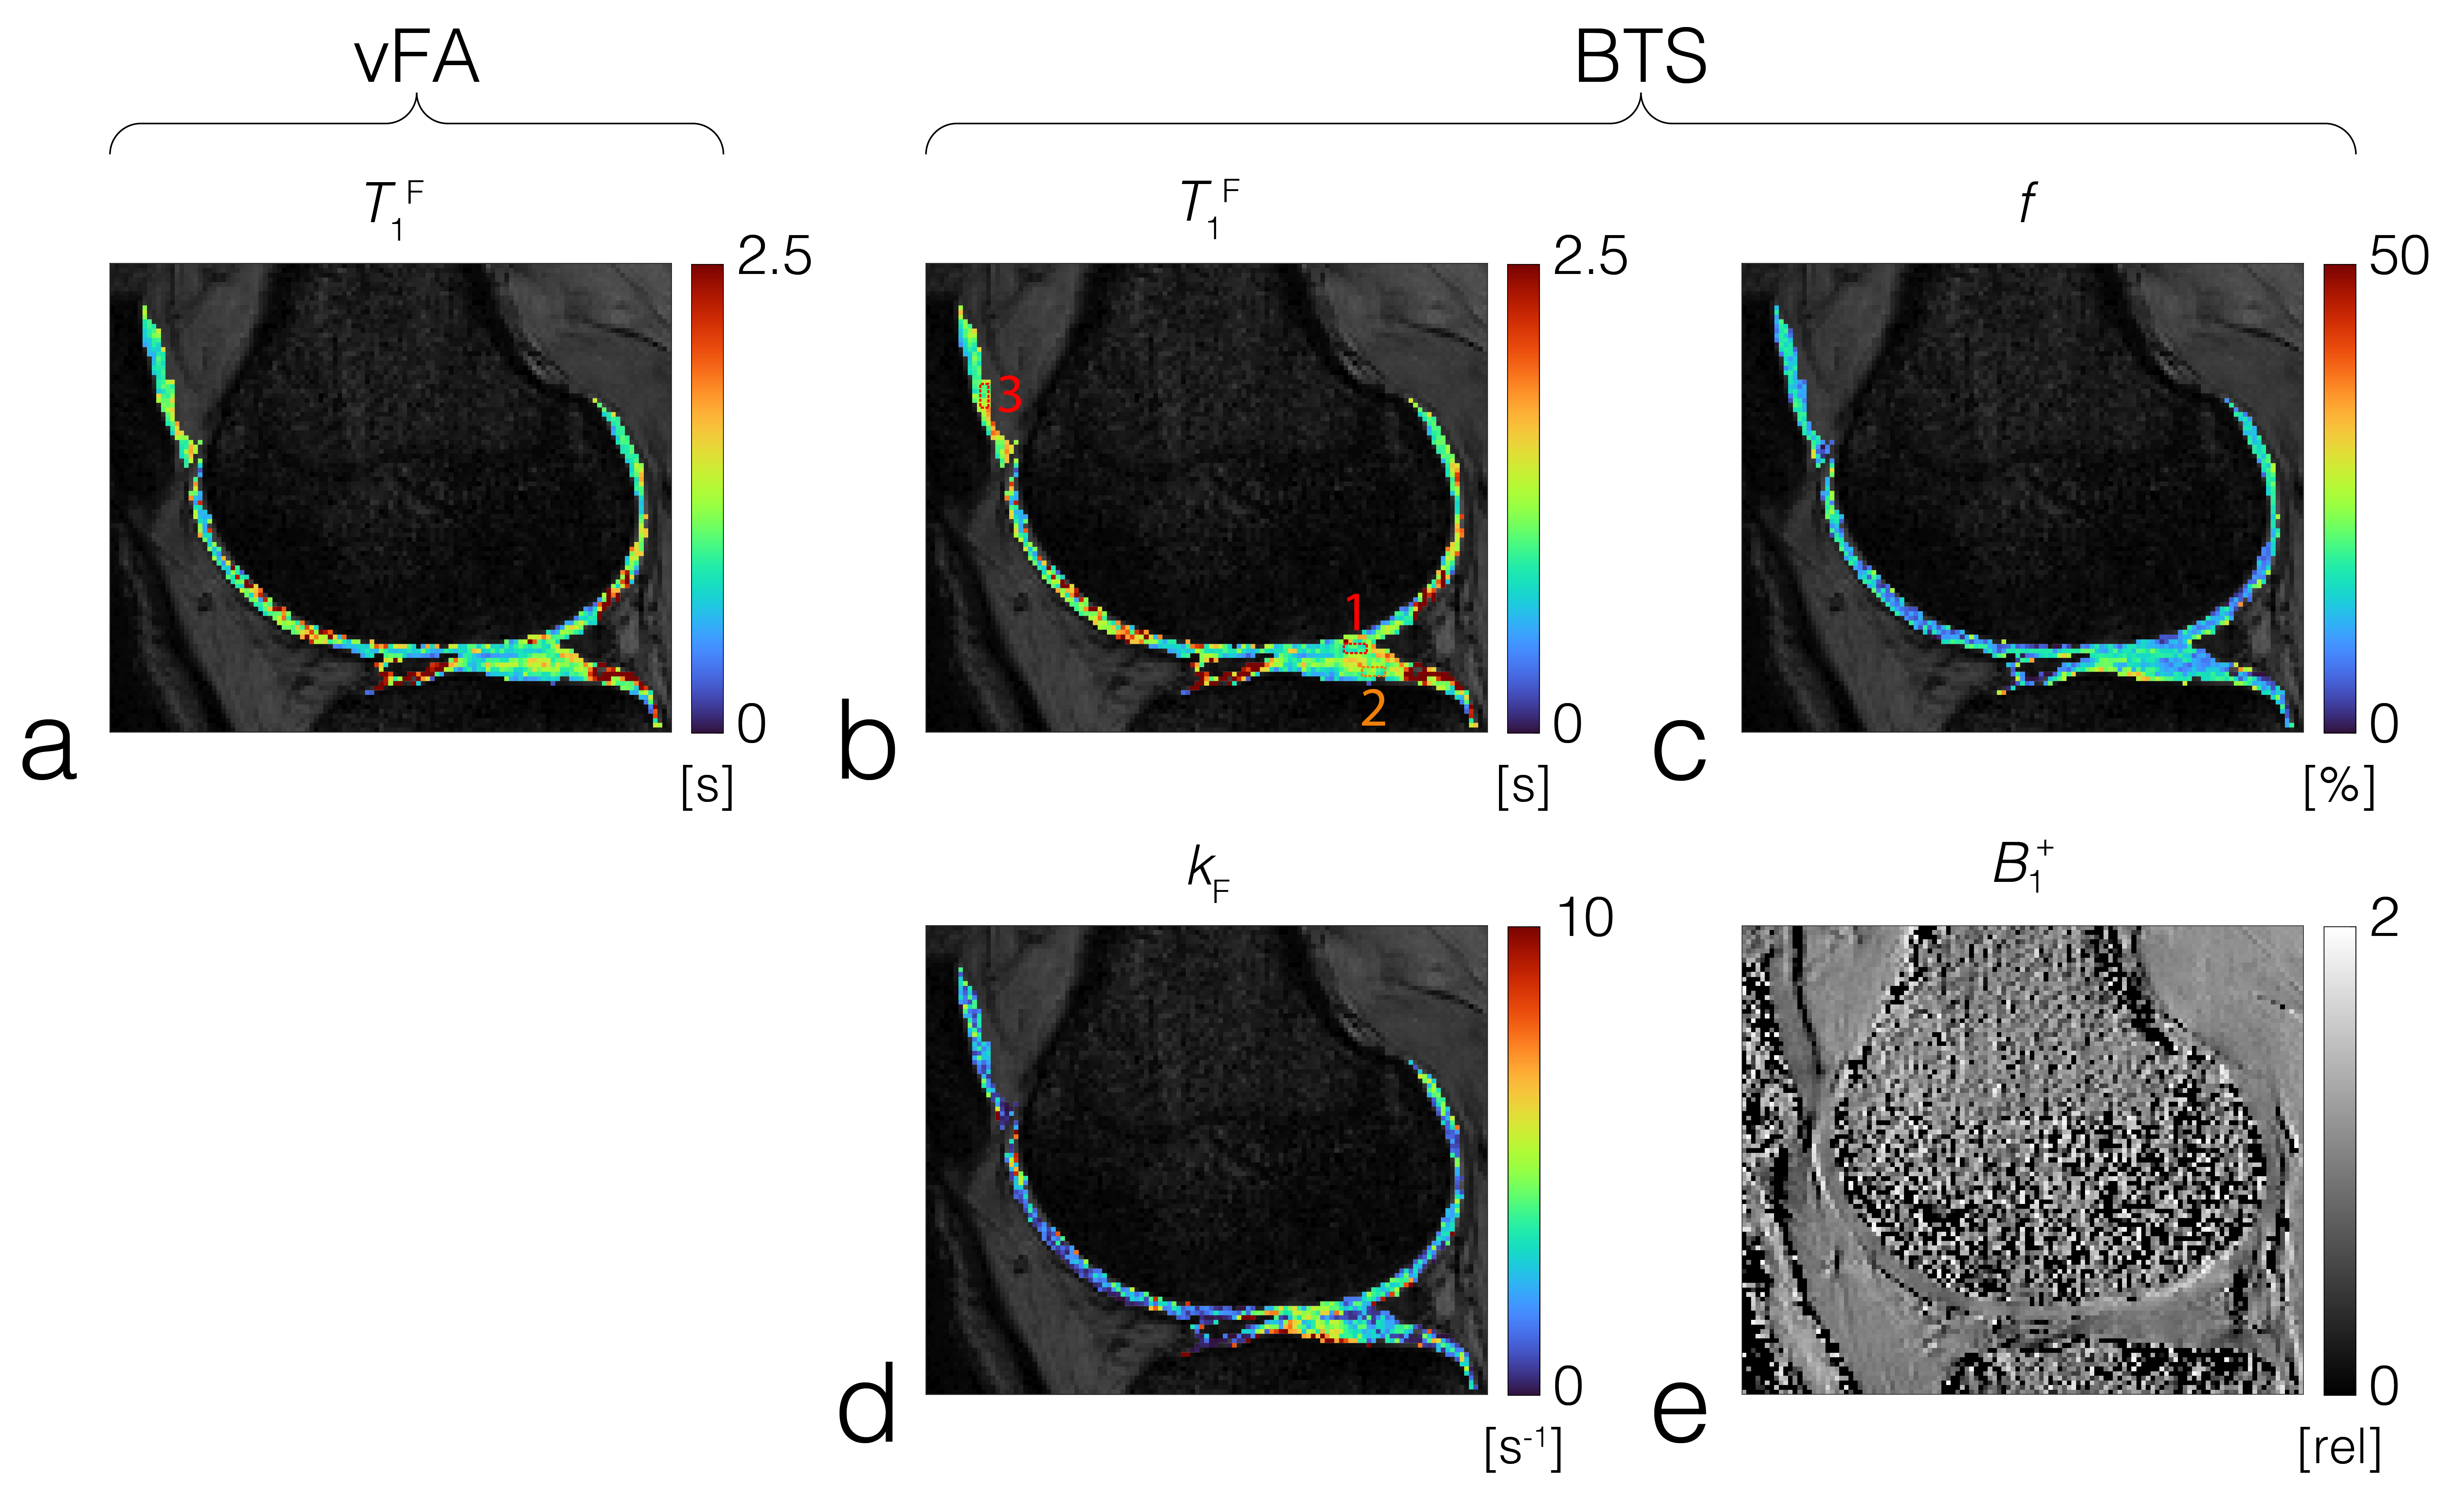

Phantom experiment: Results show f increases linearly with agar concentration (FID3A,D), while the fundamental rate constant (=kF/f) was relatively constant (FID3B,E), in agreement with previous results3. T1F estimated from vFA showed a significant difference with that estimated from BTS (FIG3C), whereby this difference increased with f(FIG3F). Representative baseline and BTS fit curves taken from voxels in each compartment, indicated by white circles (FIG3A), show good agreement with measured data (FIG3G-J). In-vivo experiment: T1F obtained using vFA (FIG4A) and BTS (FIG4B), and MT parameters f (FIG4C) and kF (FIG4D) obtained from BTS were measured in the femoral, tibial and patellar cartilage ROI regions shown as numbered dotted rectangles in FIG4B. T1F (vFA), T1F (BTS), f and kF for femoral cartilage (1):0.829s[s]/0.903[s]/12.5[%]/1.92[s-1]; tibial cartilage (2): 1.007[s]/1.050[s]/12.4[%]/2.41[s-1]; patellar cartilage (3): 1.015[s]/1.133[s]/12.9[%]/1.78[s-1], in agreement with literature4,10.

FIG 4. T1F parameter map obtained from (a) vFA and (b) BTS along with MT parameters (c) f and (d) kF of the femoral, tibial and patellar cartilage. (e) B1+ map used for the BTS process. ROI of the femoral, tibial and patellar cartilages are indicated in (b) by squares 1, 2 and 3, respectively.